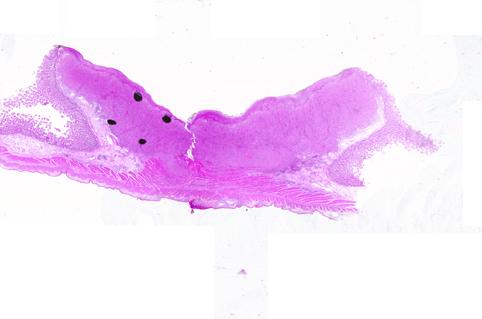

疾患(病理主体)の分類転移性腫瘍/

部位(臓器別)小腸/空腸

検査方法ミクロ

腫瘍の肉眼分類2型(潰瘍限局型)/

病変の最大径(ミリ)25〜29

腫瘍の深達度mp

多発腫瘍(同一臓器)有(同時性)

多重腫瘍(他臓器)有(同時性)